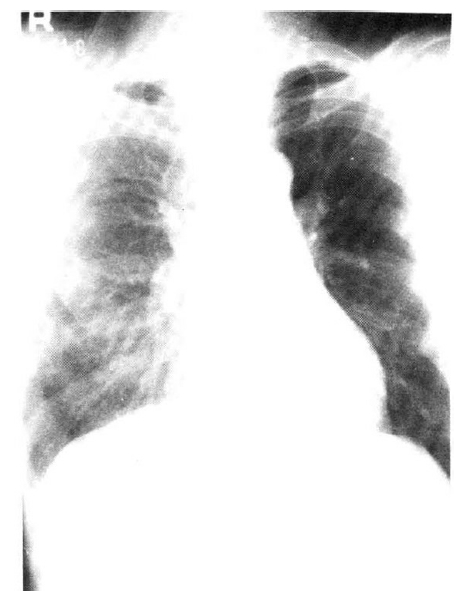

An X-ray film of the chest showed multiple nodular densities throughout both lower lung fields (Fig. 1). A computed tomographic scan of the brain and chest revealed multiple nodular and small calcified densities (Fig. 3, 4).

Afterward, the patient was treated with praziquantel 50 mg/kg/day for 15 days and discharged on the 18 th hospital day, even though he still reported some weakness, cough, and sputum production. One month after discharge, his symptoms began to improve. Six months after treatment, the subcutaneous nodules had decreased to half in size. An X-ray film of the chest revealed nearly normal conditions in the lungs(Fig. 2).